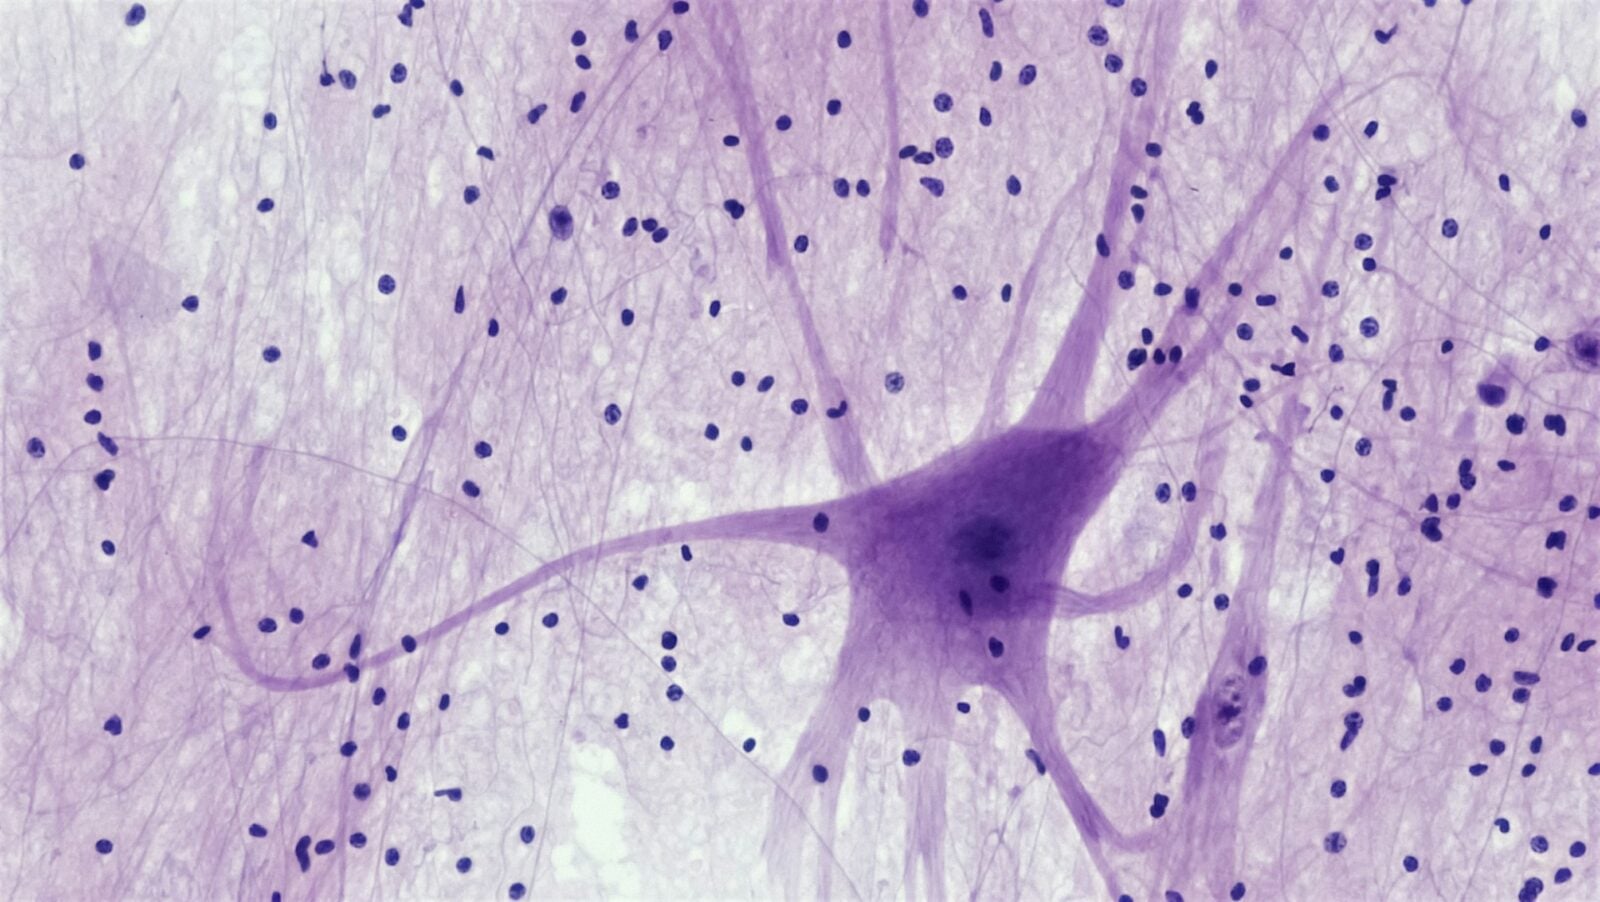

Kiedy rdzeń kręgowy ulega uszkodzeniu, zwykle tworzy się gęsta tkanka bliznowata, która tylko wypełnia ubytek, ale nie odtwarza funkcji utraconych komórek nerwowych. Wykorzystanie odpowiedniej mieszanki biomateriałów może pomóc w stworzeniu lepszego środowiska dla odbudowy nerwów.

Badanie wykazało, że hydrożel HADA/HRR wzmocniony kurkuminą i neurotrofiną-3 (NT-3), działa znakomicie. Ponieważ NT-3 jest substancją, która promuje wzrost nerwów, znacznie poprawiła funkcje motoryczne i czuciowe u szczurów oraz funkcje motoryczne u psów poprzez promowanie regeneracji nerwów. Ponadto hydrożel przekształcił tkankę bliznowatą w sprzyjające środowisko dla wzrostu aksonów.

Autorzy badania stwierdzili, że hydrożel HADA/HRR manipulował infiltracją komórek PDGFRβ+ przekształcając gęste blizny w wyrównane włókniste podłoże, które kierowało odrostem aksonów.